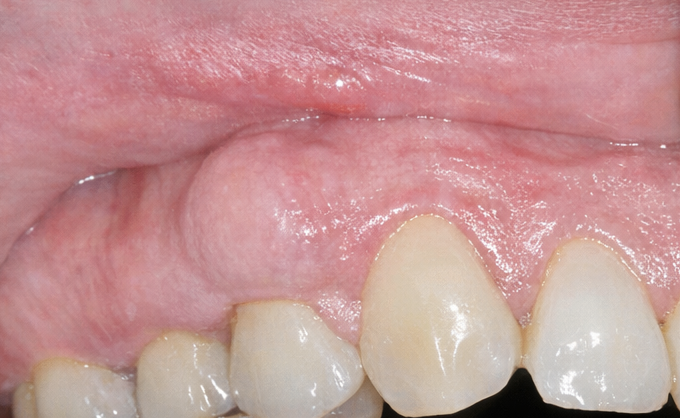

Extraoral examination did not reveal facial asymmetry or lymphadenopathy. Intraoral inspection revealed a solitary, well-defined, firm swelling on the buccal gingiva in the region of the right maxillary first and second premolars.

The lesion measured approximately 1.8 × 1.2 cm, was covered by normal-appearing mucosa, and was non-tender on palpation.

The mass was firm and immobile, suggestive of an osseous origin. There was good oral hygiene, with no significant plaque or calculus accumulation in the region. Periodontal probing around the involved teeth revealed shallow sulcus depths with no evidence of periodontal pockets. Teeth in the region were non-carious and responded normally on vitality testing.

No peripheral stigmata such as ulceration, sinus tracts, or soft tissue tags were present. The patient’s occlusion was Class I with balanced contacts and no signs of parafunctional wear.